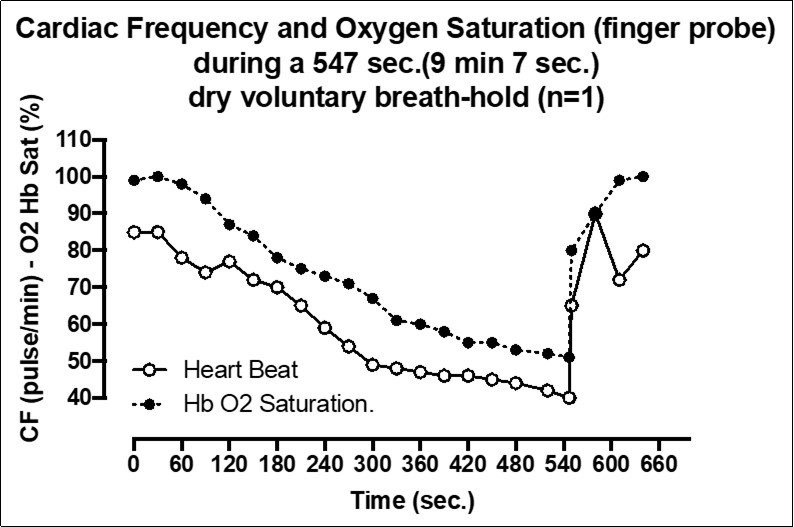

In BH-diving (as in our experiment) the extended time without breathing exposed the subject to brain hypoxia/ hypercapnia associated with a decrease of cardiac output and peripheral HbO2. The Figure 4 show the hypoxia and hypercapnia BH-diving related obtained the same day of fRNM test but during a performance even longer (9 min, 7 sec) which illustrates this aspect.

Figure 4.Cardiac Frequency and Oxygen Saturation (finger probe) during a 547 sec. (9 min 7 sec) dry voluntary breath-hold (n=1)